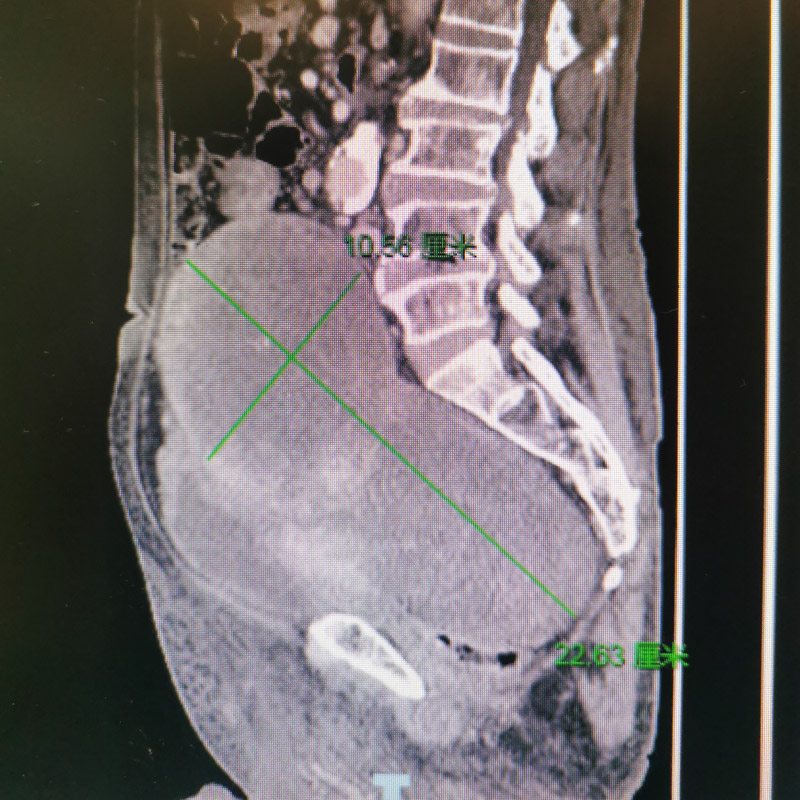

經(jīng)下肢靜脈彩超、盆腔磁共振及增強CT檢查,提示患者盆腔內(nèi)有一顆供血豐富的腫瘤,由于腫瘤過于巨大,造成直腸、膀胱及雙側(cè)髂靜脈受到了不同程度的壓迫。